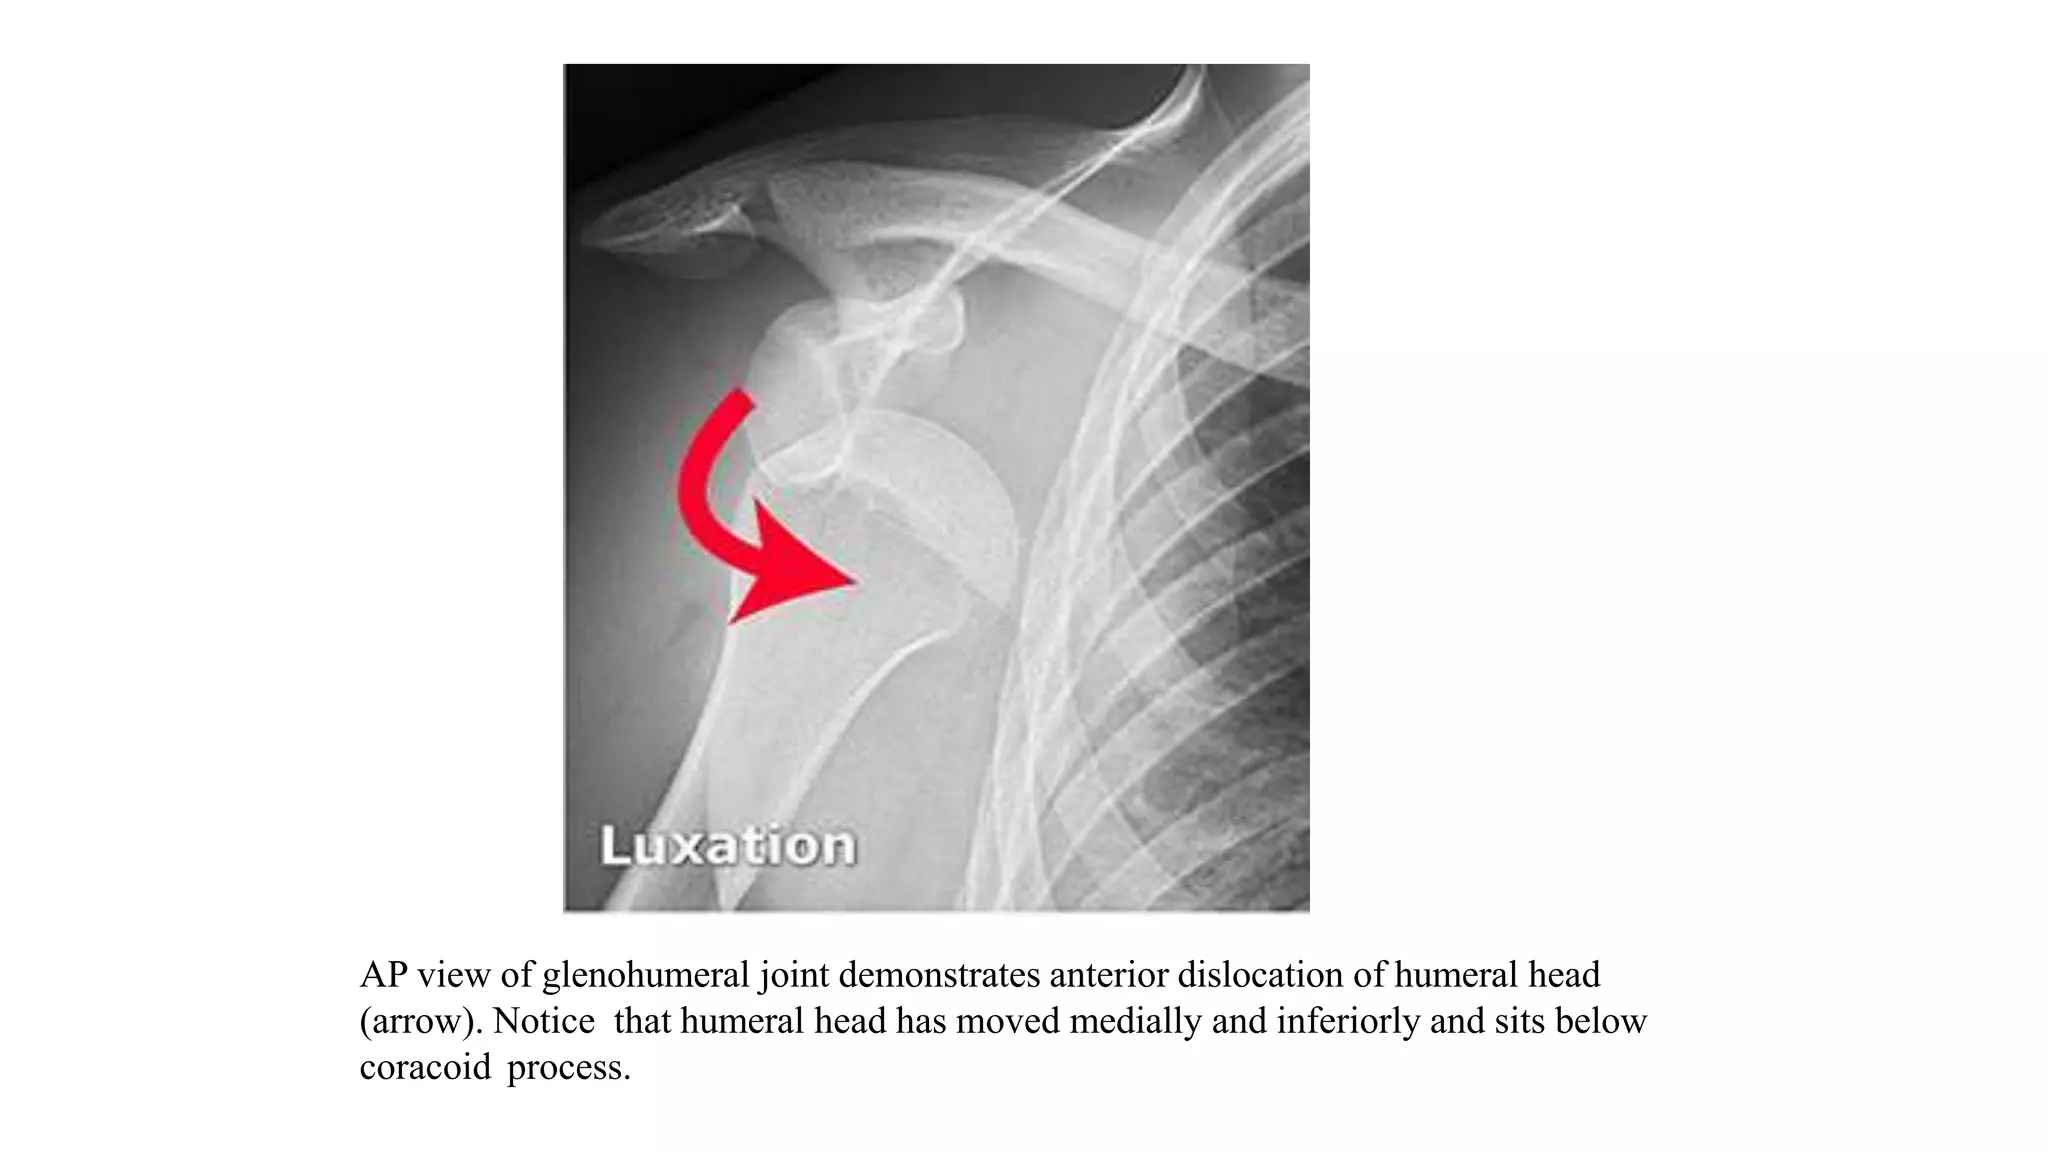

AP view of glenohumeral joint demonstrates anterior dislocation of humeral head

(arrow). Notice that humeral head has moved medially and inferiorly and sits below

coracoid process.